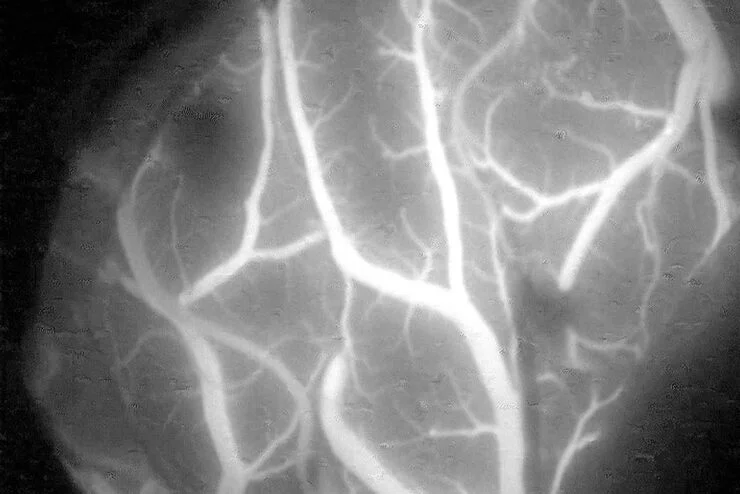

GLOW800

Filtro de fluorescência para microscópios ARveo e M530

FL800

Na videoangiografia intraoperatória com o auxílio de fluorescência, os cirurgiões podem observar o fluxo sanguíneo para determinar a permeabilidade dos vasos.